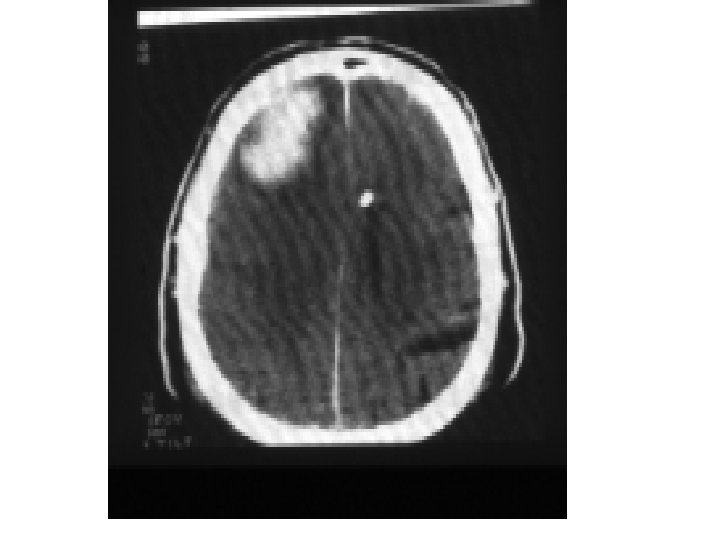

Sınıflandırma Morfolojik yapıya göre Kranial Fraktürler: Konveksite: - Linear/ parçalı - Deprese /nondeprese - Açık/kapalı Kafa tabanı: - Likör fistülü var /yok - Yedinci sinir hasarı var/ yok İntrakranial lezyonlar: Fokal: - Epidural - Subdural - İntraserebral Yaygın: - Konküzyon - Diffüz aksonal hasar

Epidural Hematom: Patogenez • Duranın periosteal tabakasının kafatasının iç tabulasından disseke olması sonucu • Meningeal arter, ven veya venöz sinüsleri çaprazlayan fraktürler • > 60 yaş ve < 2 yaş nadir görülür : Duranın periosteal tabakası sıkı bir şekilde yapışık • Linear, çökme ve diastatik fraktürler • Fraktür olmadan da EDH olabilir

EDH: Lokalizasyon ve Klinik Tablo • Temporal veya Temporoparietal – En sık görülenler – Klasik olarak: A. Meningica Media’nın kesilmesi – Bu bölgede kemik incedir …For. Spinosum – Hızlı unkal herniasyon, progresif şuur etklenmesi, kontralateral hemipleji ve N. Occulomotorius parezisi – Karşı pedinküle bası: ipsilateral hemiparezi (Kernohan bulgusu)

EDH ‘da BT’de bikonveks ( lentiküler ) görünüm